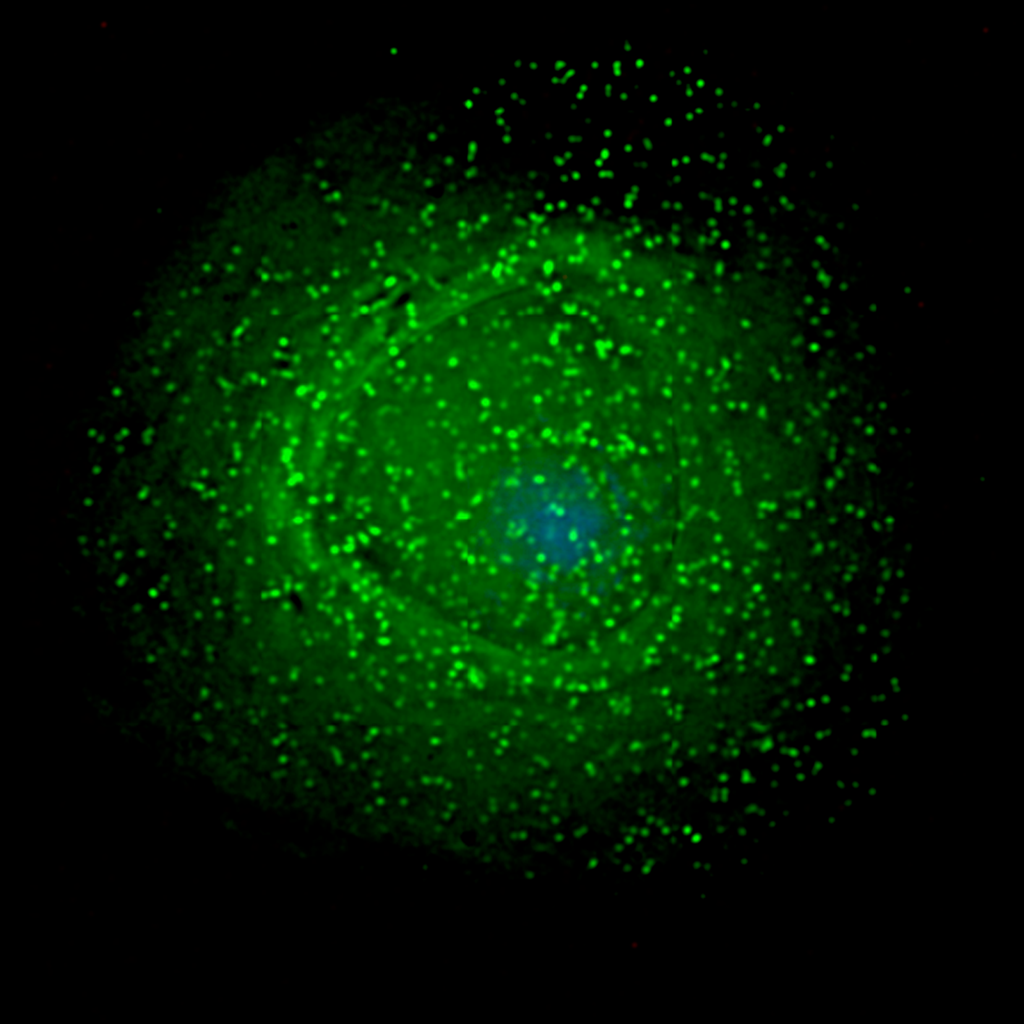

Fluorescence Microscopy: New 2-D Images Can Detect Cancer RiskPortuguese researchers have developed a new method which uses images of a protein in cells to quantify...